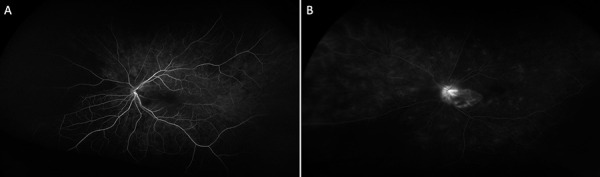

Observations: We report two cases of ophthalmic calciphylaxis presenting as (1) anterior ischemic optic neuropathy (AION) and cilioretinal artery occlusion in a 76-year-old woman with pre-dialysis kidney failure, and (2) AION with contralateral central retinal artery occlusion (CRAO) in a 44-year-old man on hemodialysis.